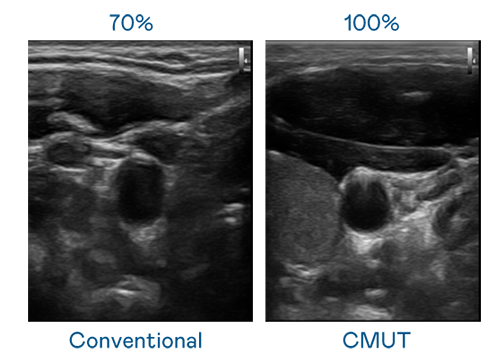

CMUT 技术是一种用电容式微机电元件来产生超音波讯号的技术。与传统 PZT 压电式技术相比,CMUT 频宽增加 30%,更宽频的超音波讯号让影像解析度大幅提升,是实现高影像品质医疗超音波扫描、促进精准医疗发展的关键技术。

大频宽带来超清晰影像

超音波影像的解析度高低,首先取决于探头能发出的讯号频宽。豪门国际 CMUT 可提供高清晰的超音波讯号,提供高频宽、高灵敏度、影像纹理细节更高的超音波影像,协助医护人员缩短影像判读时间及利用精准的医疗影像进行诊断。